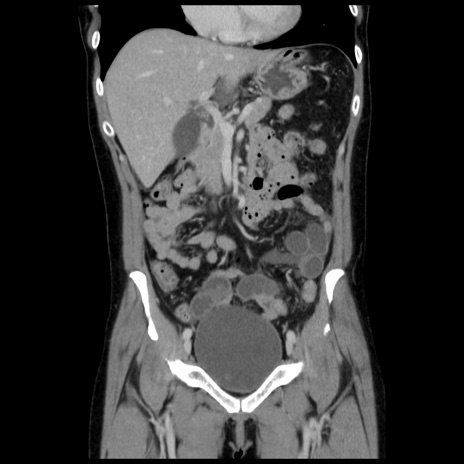

症例10(冠状断像)

【症例】 50歳代女性

【主訴】 腹痛

【現病歴】前日生レバーを食べた。今朝に排便あり。 昼前に突然発症の腹痛を生じ、当院救急外来を受診した。

【既往歴】 子宮筋腫にてで子宮全摘後

【身体所見】 意識清明、腹部:平坦、軟、下腹部やや左を中心に圧痛・反跳痛あり、筋性防御あり

【データ】WBC 7800、CRP 0.07